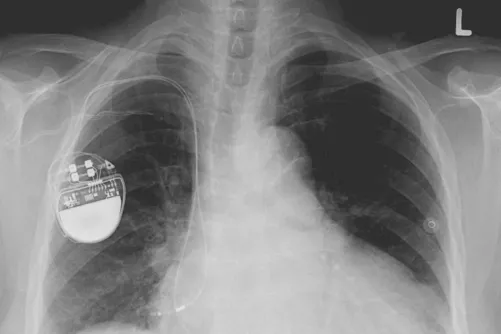

A szívünk az egészségünk központja, amelynek már egy kis meghibásodása is nagy hatással lehet teljes szervezetünkre. Hazánkban kimagasló azon betegek száma, akik érintettek valamilyen szív-érrendszeri...

A pitvarfibrilláció a leggyakoribb krónikus szívritmuszavar. A teljes népesség mintegy 2 százalékát érinti és a 40 év feletti felnőttek egynegyedénél alakul ki valamikor az életük folyamán. A betegség...